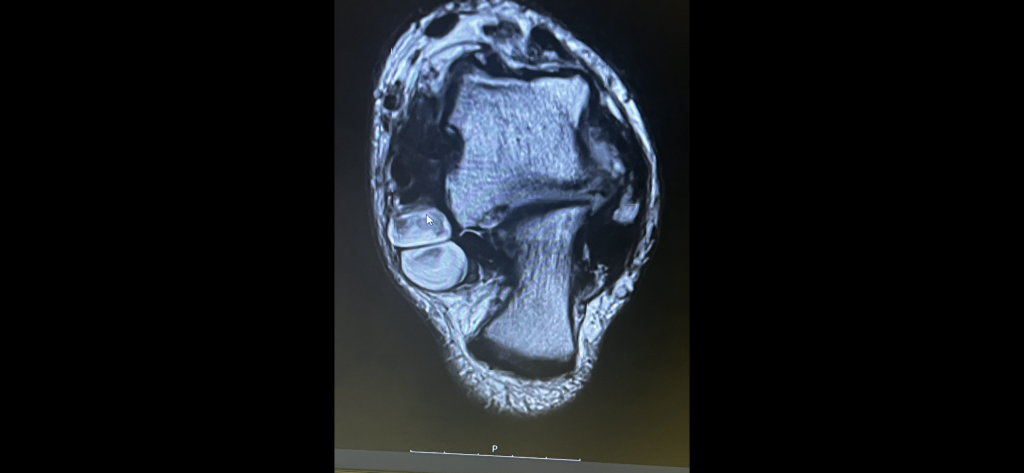

Dr. Cody was the third MD I saw in reference to an ankle condition I had. She explained what was wrong with my ankle and what procedure she would do. In a matter of three weeks she requested all of the required imaging and performed surgery. I wish I would have contacted Dr. Cody from the onset of my symptoms. I would wholeheartedly recommend her to anyone who has any ankle issues.